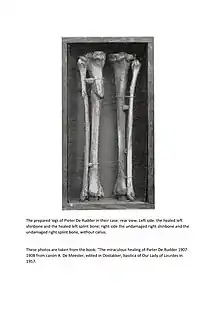

Pieter De Rudder (July 2, 1822 in Jabbeke – March 22, 1898), in many French books Pierre De Rudder, in English Peter De Rudder.[1] His recovery from a broken leg is one of the most famous recognized Lourdes miracles (a bronze cast of his bones is exhibited in the Lourdes Medical Bureau[2]), although it is not supposed to have occurred in Lourdes itself, but in a sanctuary of Our Lady of Lourdes at Oostakker near Ghent (Belgium, East Flanders).